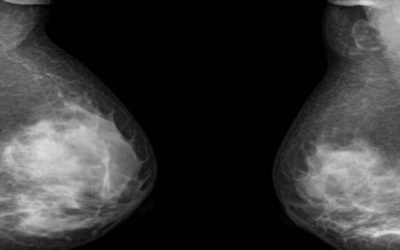

Diagnosing breast cancer

Mammograms are a safe, effective way to detect the presence of breast cancer in women. But doctors recommend most females should start getting mammograms after the age of 40 in part because the procedure involves small doses of ionising radiation. While the risk of...